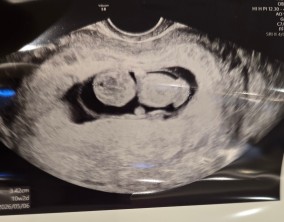

빠르게 찾아온 기적, 로또 둥이

그 모든 과정 속에서 이유정 원장님께서 따뜻하게 공감해주시고, 제 몸 상태에 맞춰 치료 플랜을 세심하게 짜주신 덕분에 좋은 결과가 빠르게 찾아온 것 같아요.